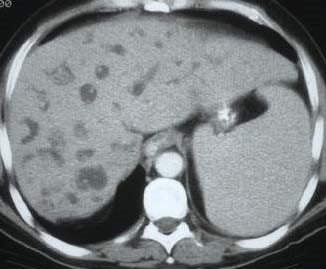

- Diaqnozu dəqiqləşdirmək üçün Qc venaları yoxlanılmalıdır. Bunun üçün dopler USM, KT-angioqrafiya, MRT-angioqrafiyalar və ya kontrastlı venoqrafiya edilir.

- Görüntüləmədə Qc venalarının trombotik tutulması diaqnozu dəqiqləşdirən əlamətdir.

PVT diaqnozunu dəqiqləşdirmək üçün portoqrafiya aparılır – Doppler USM, KT və ya MRT angioqrafiya.

- Kontrastlı müayinələrdə damarda tromb və ya kavernoz transformasiya

Baddi-Kiari sindromu böyük qaraciyər venalarının tıxanması nəticəsində meydana gələn venoz durğunluqdur, qaraciyər venaları ilə yanaşı aşağı boş venada da tıxanma ola bilir. Tromboz, fibroz, membran və infiltrasiya (şişlər, iltihab) ən çox rast gələn səbəbləridr. Erkən mərhələlərdə kəskin hepatit və kəskin qaraciyər yetməzliyi, xroniki mərhələdə sirroz və PH meydana gələ bilir. Diaqnozu üçün tomoqrafiya və kontrastlı angioqrafiya lazım gəlir, Qc venalarının trombotik tutulması diaqnozu təsdiqləyir. digər xarakterik əlaməti birinci seqmentin hipertrofiyasıdır. Erkən mərhələdə dekompressiya (cərrahi və stend) sirroz əmələ gəldikdə isə transplantasiya ön planda tutulur.

Qaraciyər venalarının görünməməsi, kontrastlaşmaması və ya trombla tıxanması.